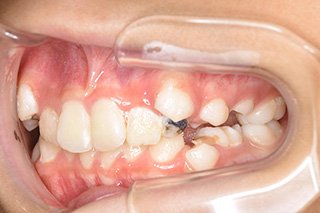

顎顔面矯正症例 11歳女児 Case

| 主訴 | 永久歯が変な所からはえてきている|顔貌 | |

|---|---|---|

| 施術内容 | 矯正1期治療 | |

| 治癒期間 | 1年5ヶ月間 | |

| 費用 | 459,200円(税込) | |

| リスク・ 副作用 | 痛みを伴う | |